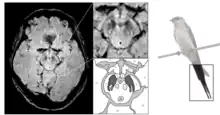

Le diagnostic de maladie de Parkinson est habituellement clinique. En théorie, la certitude du diagnostic n'est obtenue que par l'étude histologique du cerveau mais les critères diagnostiques actuellement définis permettent de faire le diagnostic sans trop de difficultés. Le scanner cérébral par tomodensitométrie des personnes atteintes de la maladie de Parkinson est habituellement normal[121]. L'imagerie par résonance magnétique sensible au fer (IRM T2*) peut être utilisée dans un cadre diagnostique. En effet, le fer peut être témoin de la mort cellulaire et le signal T2* diminue en présence de fer tandis que son inverse (R2*) augmente[122]. Dans la maladie de Parkinson, il existe une concentration en fer trop importante par rapport à la moyenne pour le même groupe d'âge au sein de la substance noire du fait de la perte de neurones dopaminergiques[123]. De plus, l'imagerie pondérée en fonction de la susceptibilité est elle aussi un marqueur fiable de la présence de fer intracérébral en étant à la fois sensible et spécifique à la maladie[124]. L'IRM T2* et l'imagerie pondérée en fonction de la susceptibilité sont toutes deux capables d'afficher le signe d'effacement de la queue d'hirondelle (swallow tail) dans la substance noire dorsolatérale. La tomodensitométrie et l'IRM sont également utilisées, en pratique clinique, pour écarter d'autres maladies pouvant engendrer un syndrome parkinsonien telles que l'encéphalite, les AVC chroniques, les tumeurs des ganglions de la base et l'hydrocéphalie[121].